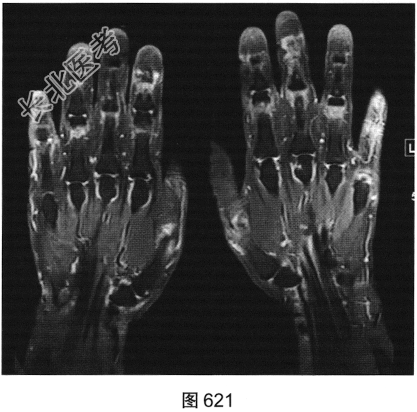

- 简答题2、患者行双手X线及MRI检查,见图619~图622。请问X线平片及MRI图像有哪些阳性表现?